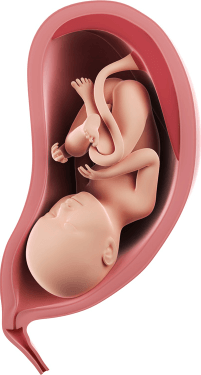

Развитие ребенка

35-недельный ребенок чувствует себя очень уютно в вашей матке. Раньше у него было место для кувырков и ударов ногами, но теперь движения крохи кажутся более сдержанными. Это связано с тем, что места малышу не хватает, и он может только ворочаться или немного выпрямлять ручки и ножки. Если малыш находится в головном предлежании, наибольшая активность ощущается под ребрами (если он шевелит ножками) и в районе пупка (если это ручки). Если это тазовое предлежание, малыш еще может перевернуться головкой вниз, но возможно, что останется в таком положении и до родов.

Тот факт, что ваш ребенок почти готов появиться на свет, не означает, что он больше не развивается. Эти последние несколько недель очень важны для того, чтобы у всех органов вашего ребенка была возможность полностью созреть, малыш набрал массу за счет мышц и жира, прежде чем появиться на свет. Каждую неделю вес малыша прибавляется примерно на 200-220 г. сейчас он может весить около 2300-2500 граммов. Рост малыша составляет сейчас около 45 см. с этого периода рост малыша прибавляется незначительно, а вот вес он набирает быстро.

Ваш ребенок много тренирует сосательный рефлекс, так как очень скоро ему предстоит впервые приложиться к вашей груди. Пока малыш располагается не очень низко, но постепенно головка плода будет опускаться ниже ко входу в малый таз.

Почки вашего ребенка теперь полностью созрели и производят стерильную мочу, которая выделяется из мочевого пузыря и смешивается с остальной частью околоплодных вод. Если у вас будет мальчик, его яички должны опуститься вниз, в мошонку.

Большая часть прибавки в весе ребенка на 35 неделе происходит за счет жировой ткани, что поможет ему после родов регулировать температуру. Плечи ребенка также набирают значительное количество жира, который смягчит эту область во время родов.